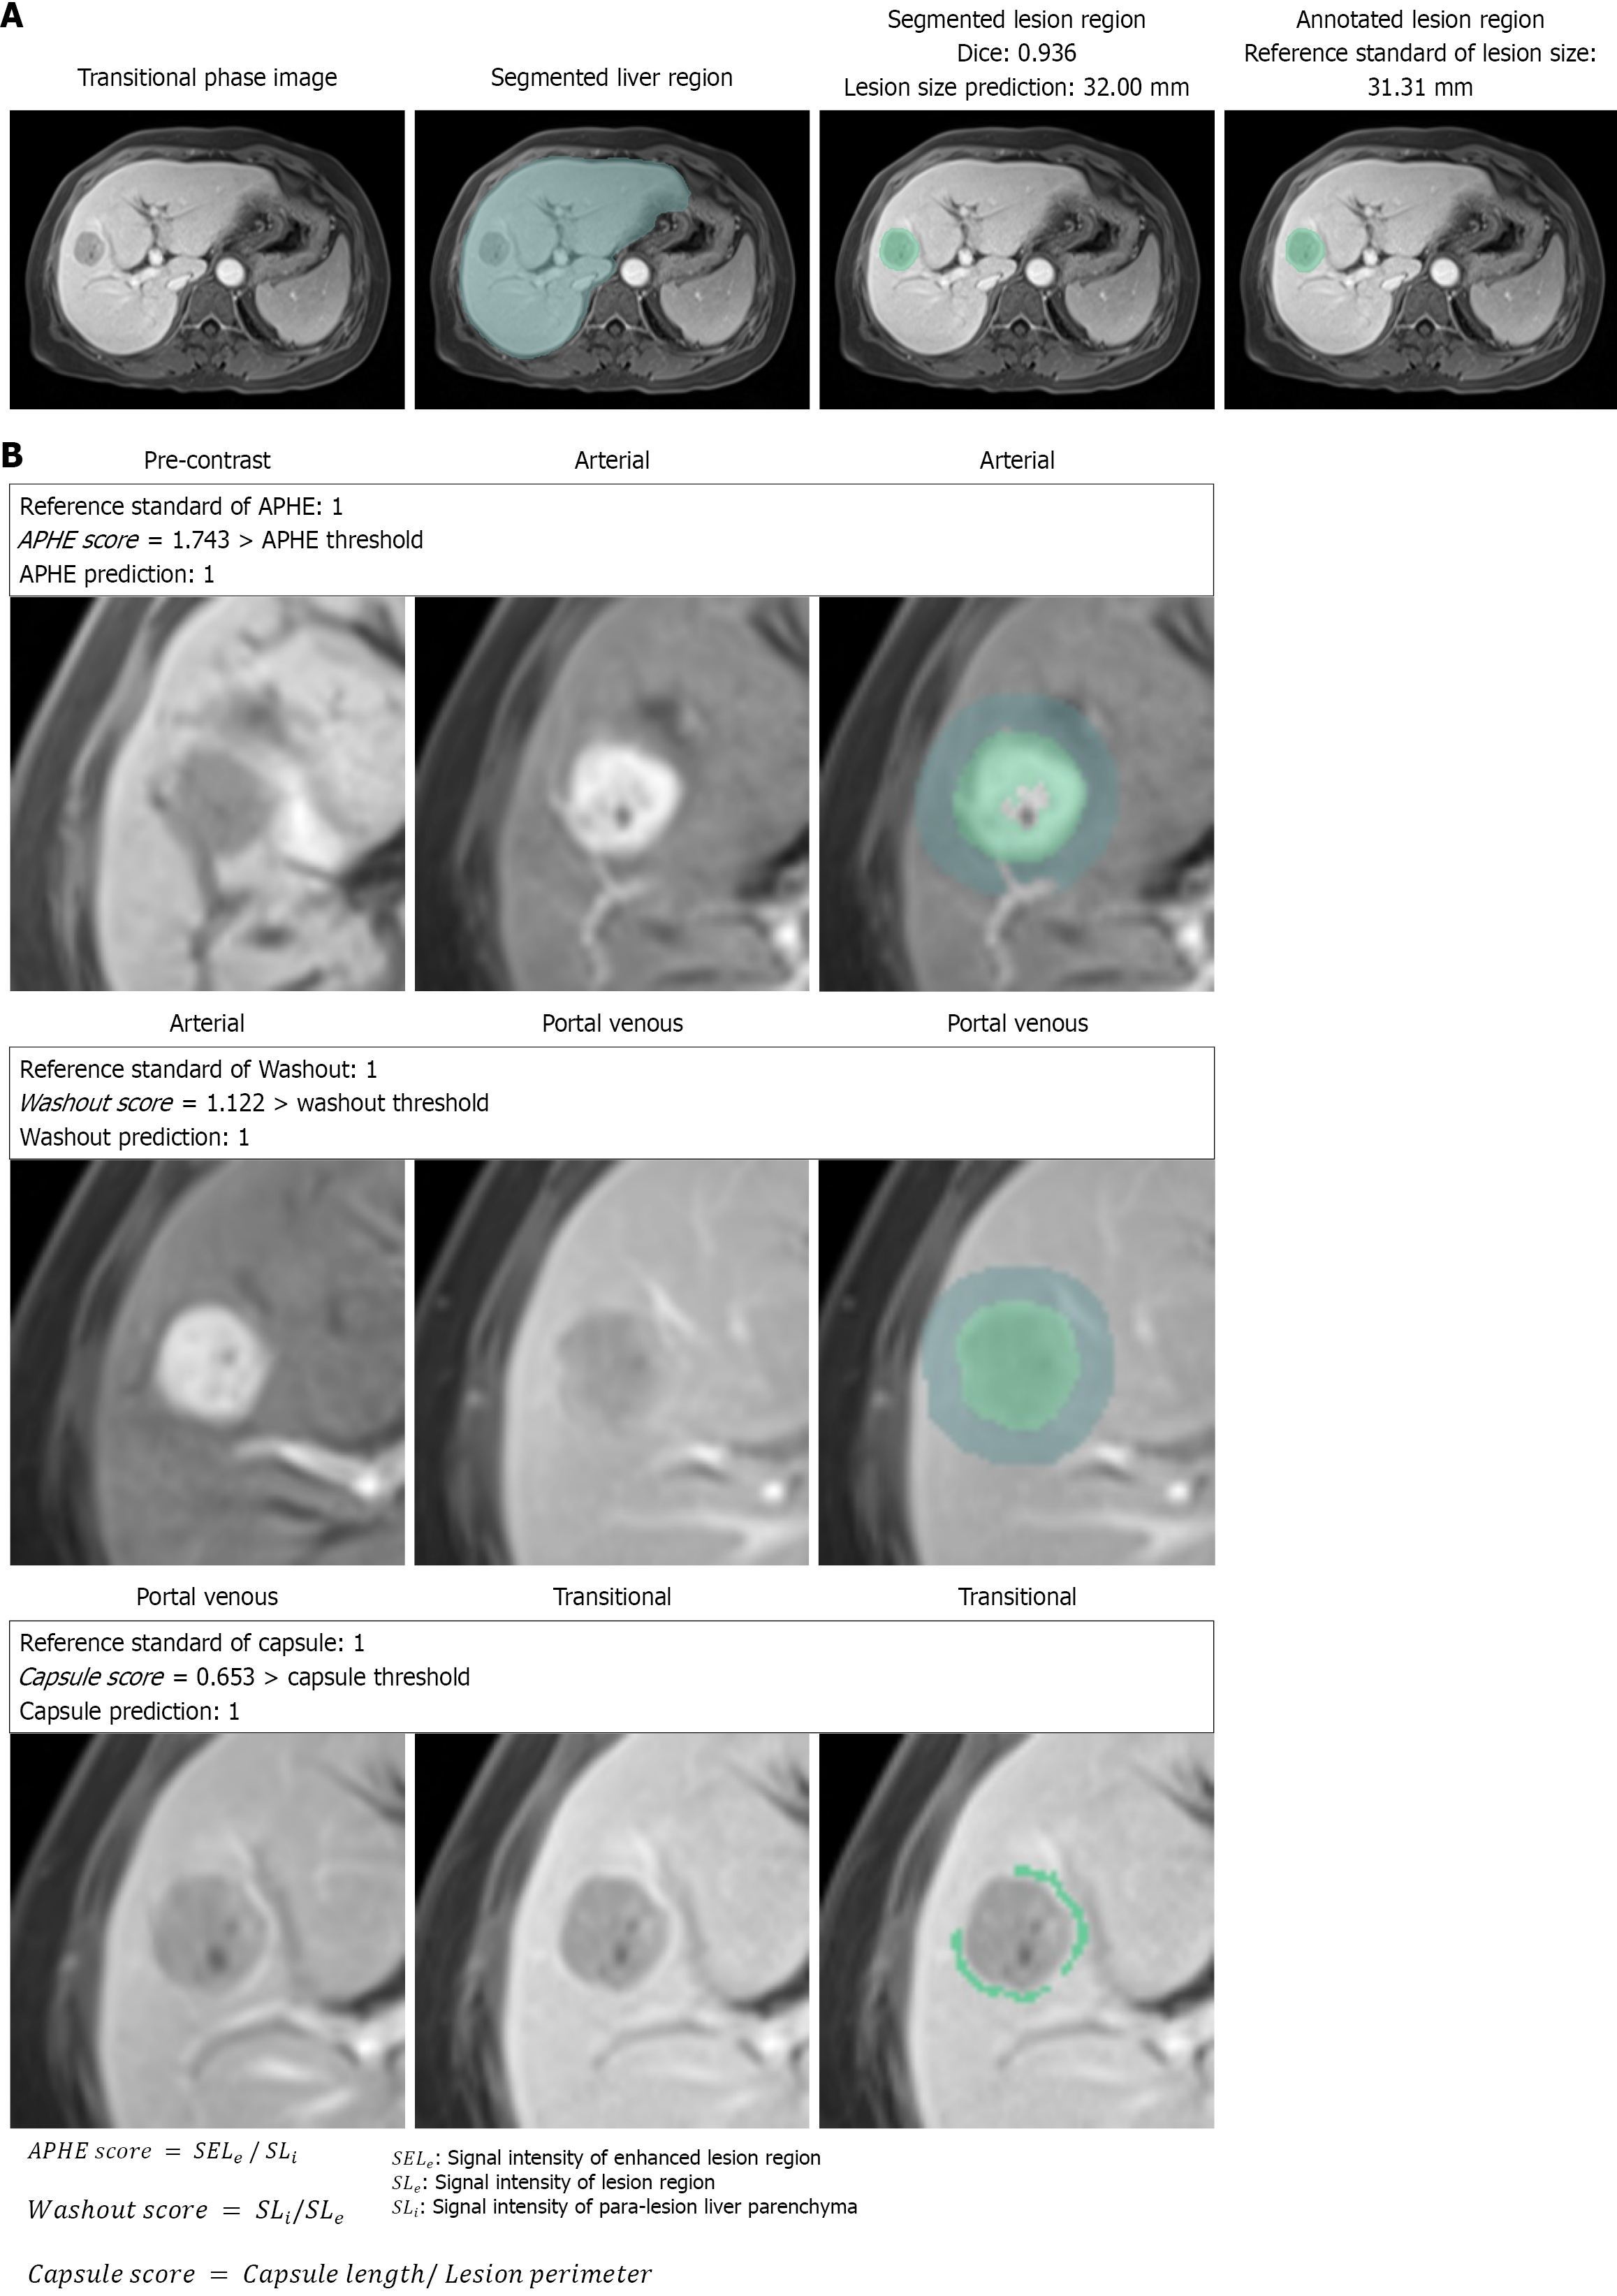

Figure 4 Visualization results.

A: Liver and lesion segmentation; B: Arterial phase hyper-enhancement (top), washout (middle), and capsule (bottom) characterization. All these regions are model outputs. APHE: Arterial phase hyper-enhancement.